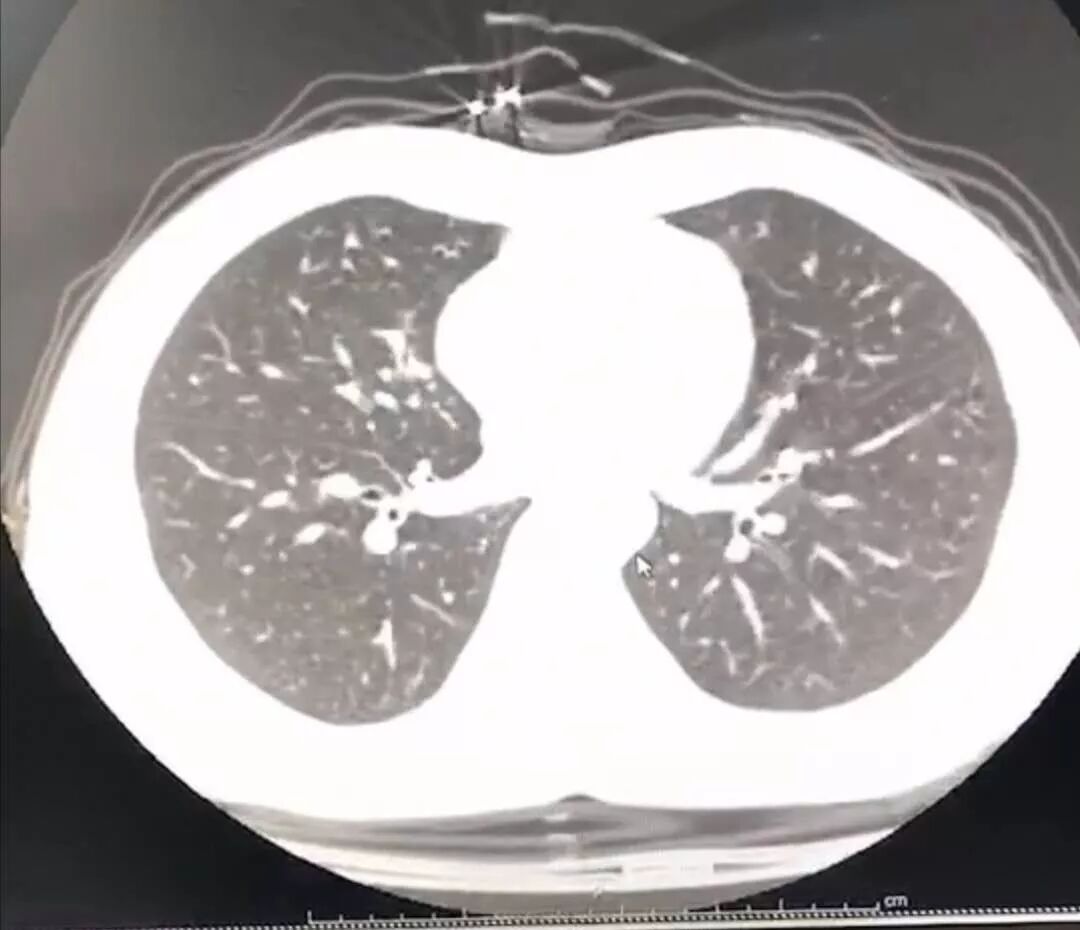

于是拖著沉重的步伐,我又從家里出發(fā)去醫(yī)院做胸部CT。幸運(yùn)的是肺部還沒(méi)有出現(xiàn)病毒性肺炎的特征性影像學(xué)表現(xiàn),說(shuō)明就算是新型冠狀病毒感染,目前還屬于輕型,沒(méi)有實(shí)質(zhì)性地累及肺組織。